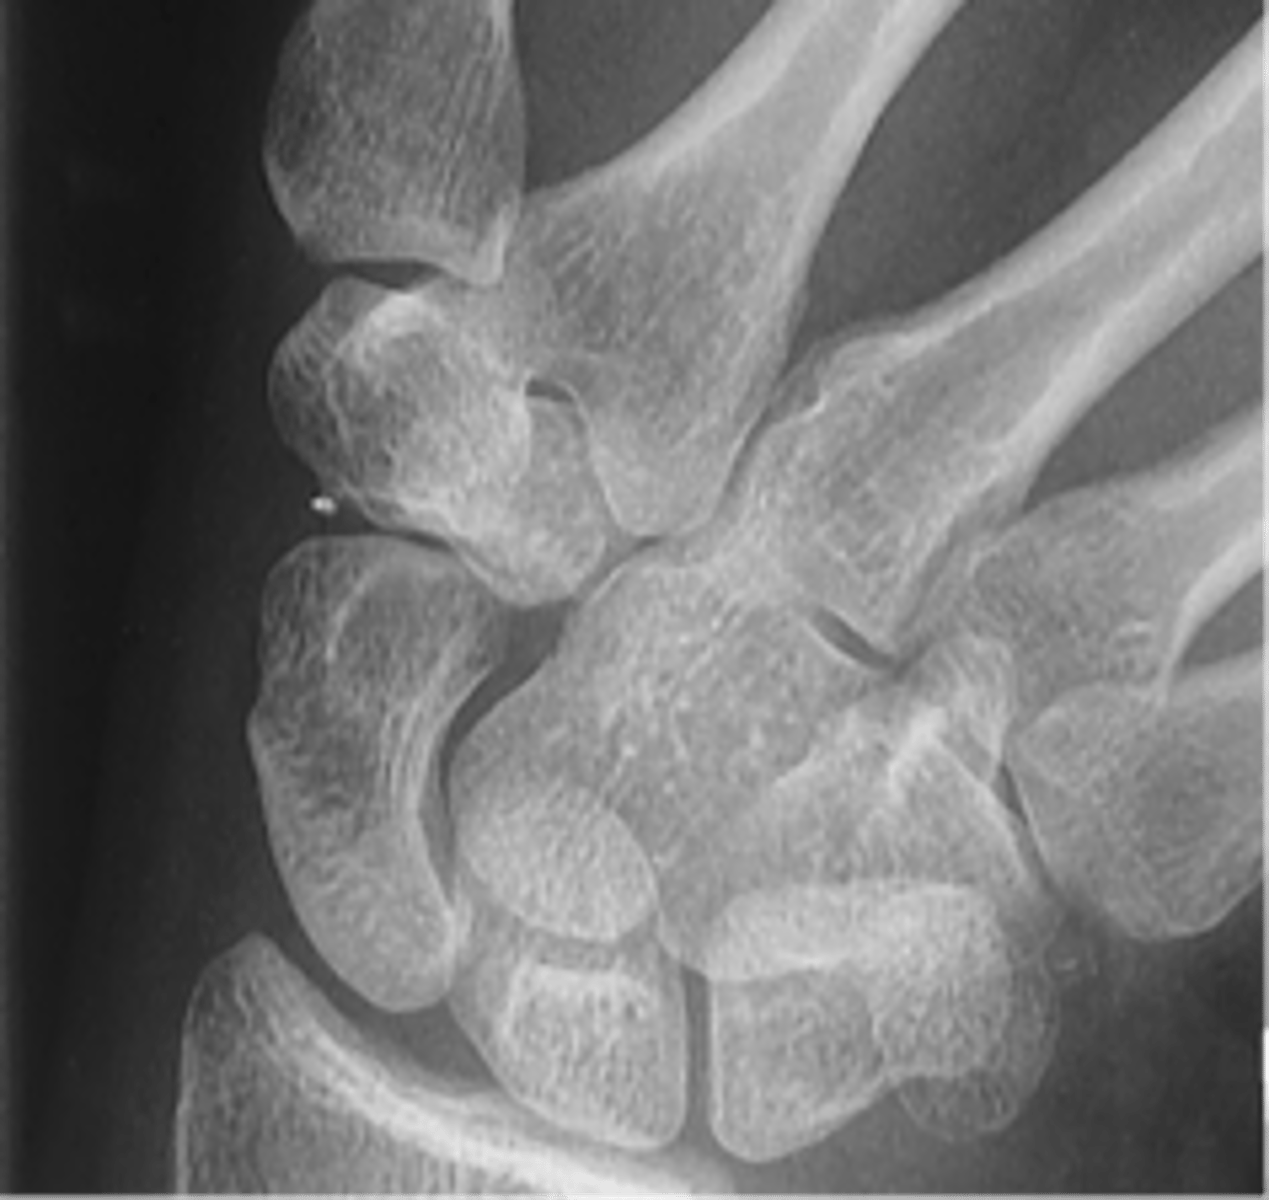

PA Axial Scaphoid

PA scaphoid modified stretcher

scaphoid fat pad